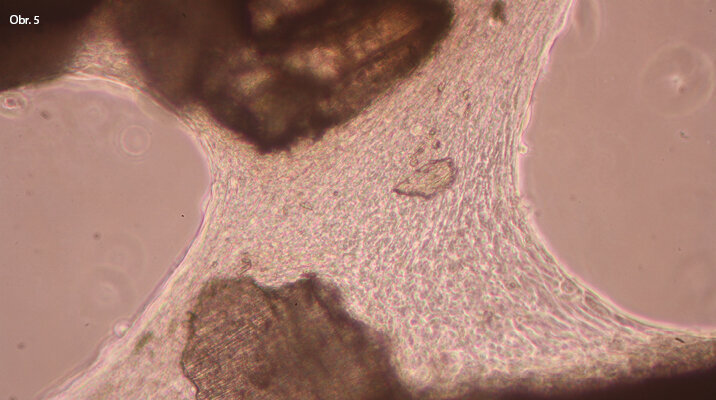

Mezi zrny tvrdé zubní tkáně se poměrně rychle (cca do 24 hodin) vytváří ucelený buněčný můstek, což může znamenat rychlou tkáňovou reakci

Vedle materiálů umělých, obvykle slitin kovů, popřípadě upravených plastických hmot, je však i zcela reálná cesta k využití buněk či orgánů tělu vlastních. To platí nejenom pro aplikace implantologické, ale i pro celou oblast reparace ať již tkáňové nebo buněčné. Jednou z nich je metoda využití dentinu pro augmentaci kostní tkáně, která je už v současnosti využívána ve stomatologii. Její princip je v rozemletí očištěného zubu na úlomky velikosti přibližně 300 μm a jejich aplikaci do zubní jamky, kde tento materiál prostor vyplní a umožní po krátké době další operační zásahy. Jde tedy o skutečný biomateriál s okamžitou aplikací, popřípadě o jeho uchování k aplikacím pozdějším.

Otázkám přijatelnosti rozemleté zubní tkáně byla věnována pozornost i na vývojovém pracovišti stomatologické kliniky LF MU v Brně a v Laboratoři tkáňových kultur Jihočeské univerzity v Nových Hradech. V podmínkách in vitro byla potvrzena hypotéza o přijatelnosti pomleté tvrdé zubní tkáně kostními buňkami, pochopitelně v modelových pokusech. Bylo nastoleno mnoho dalších výzkumných otázek, které jsou postupně řešeny nejenom na úrovni laboratorní, ale i klinické.